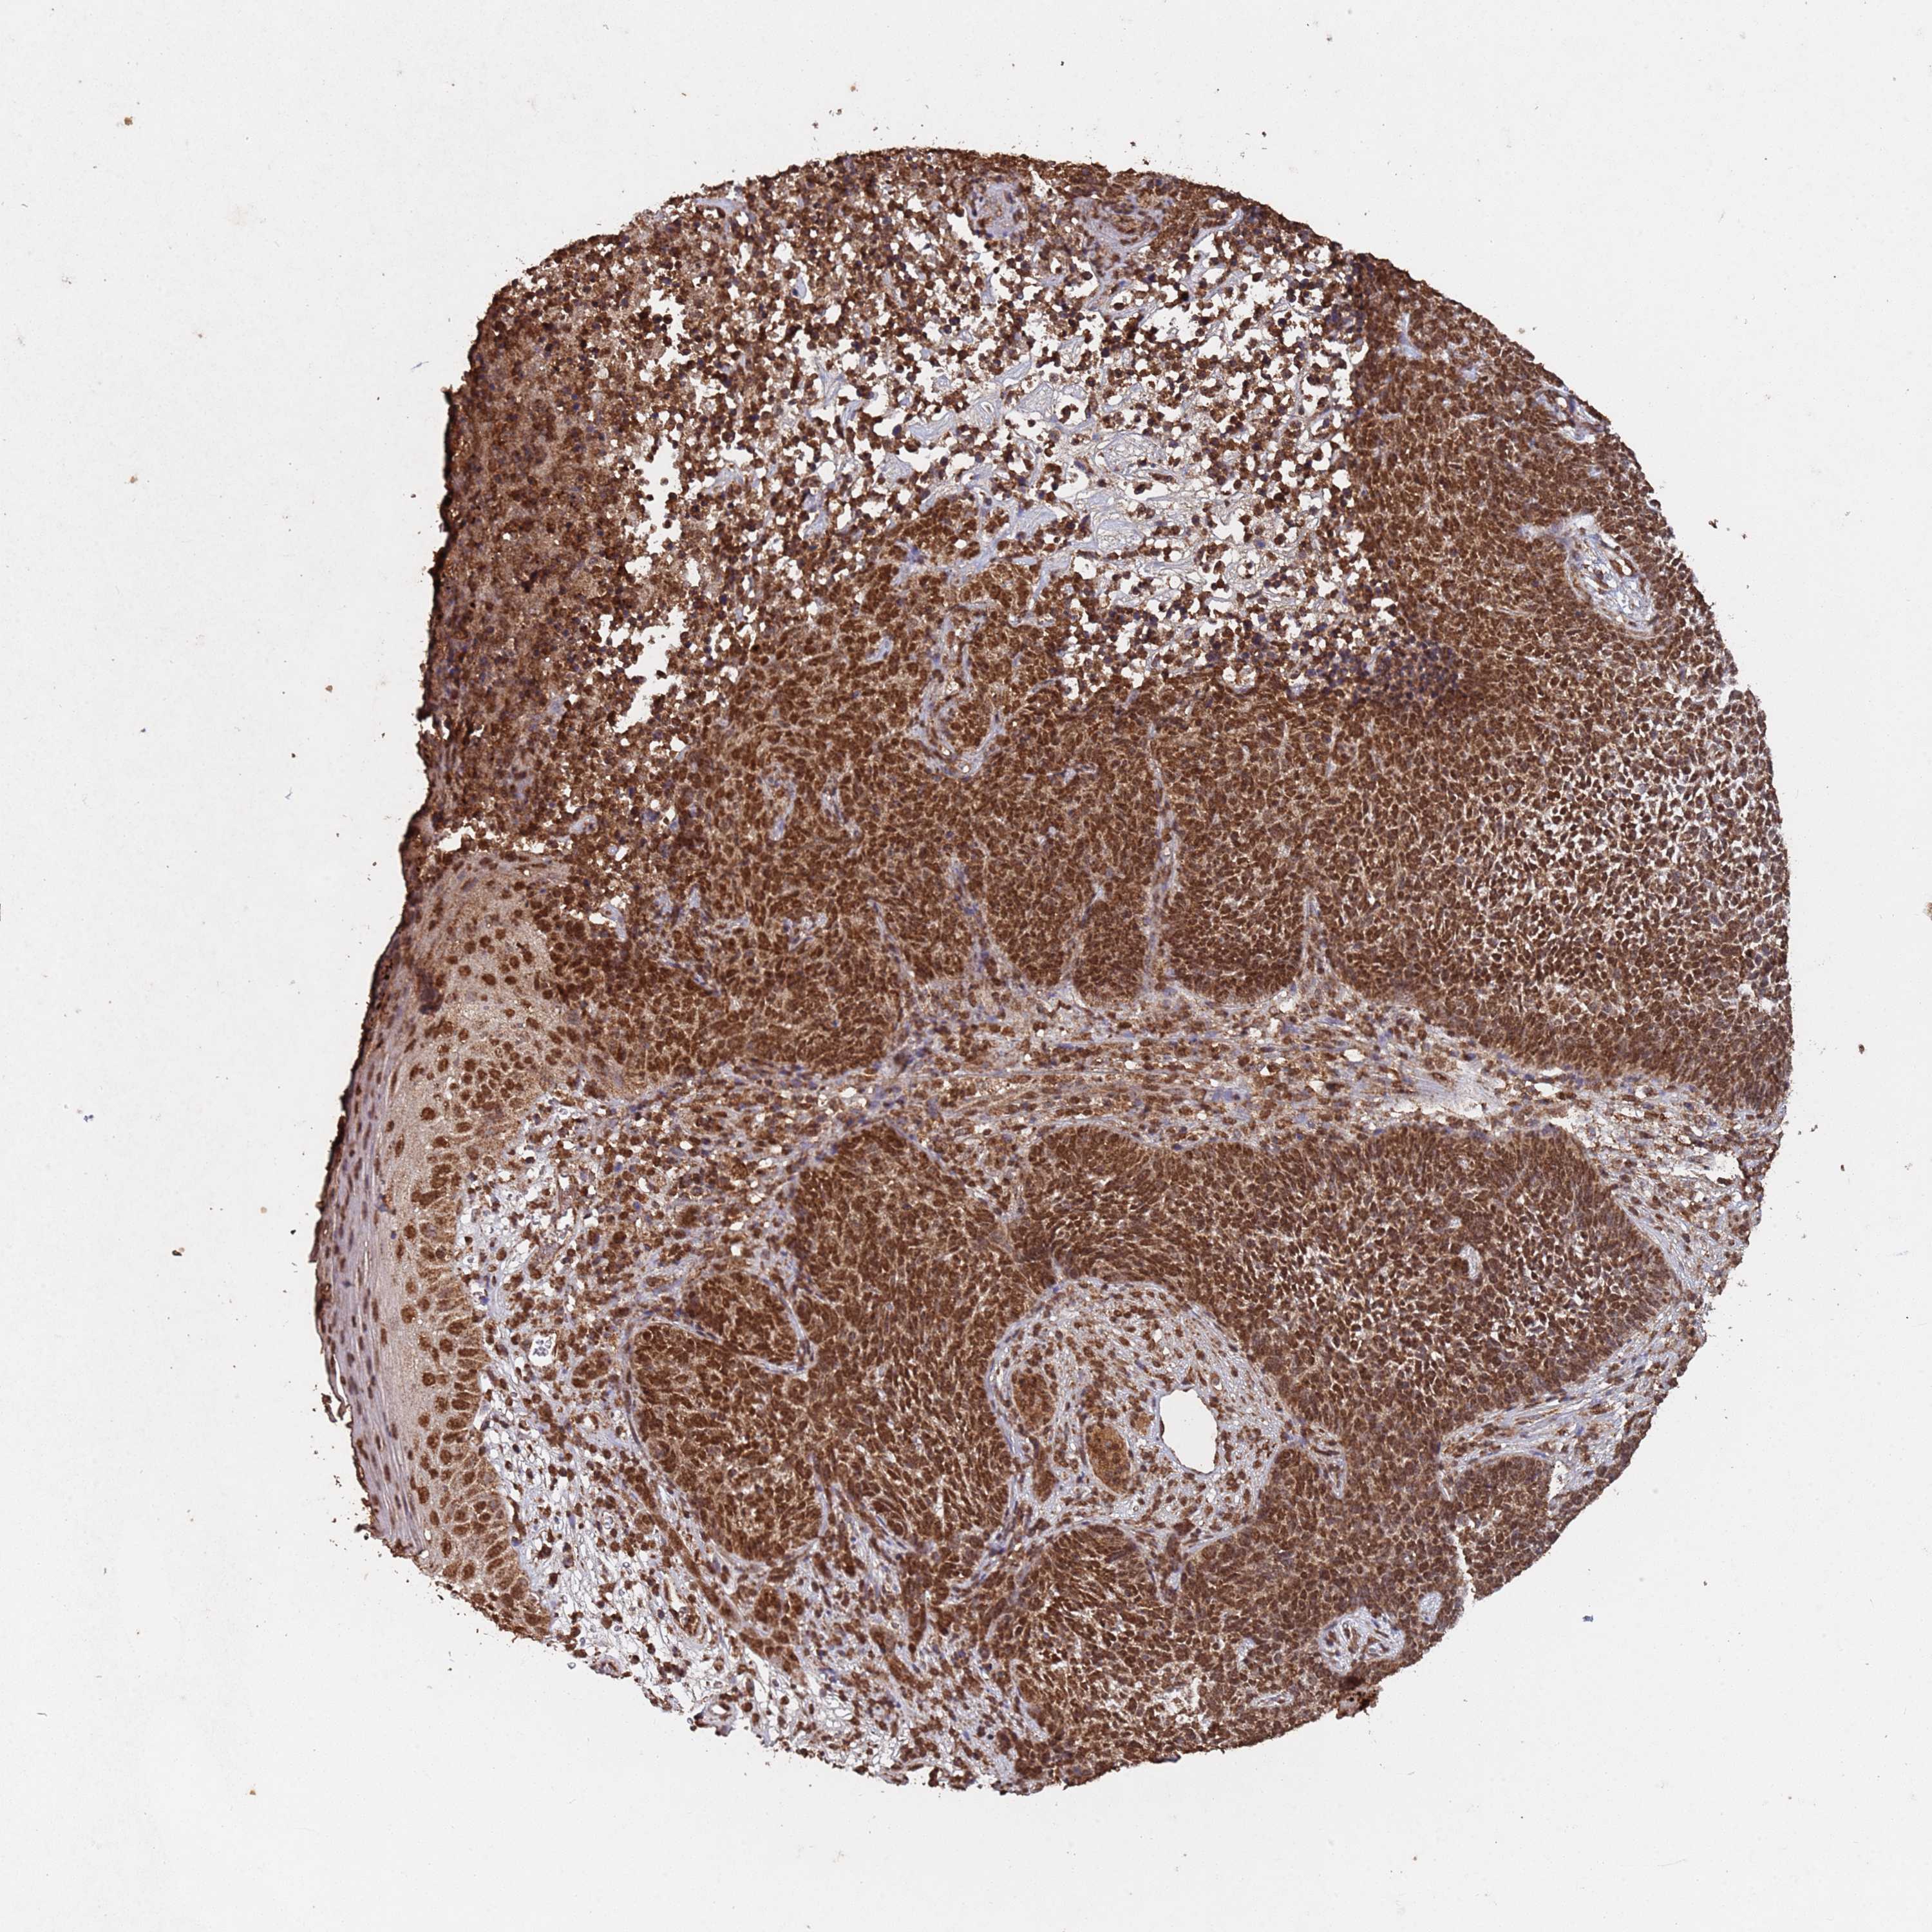

CANCER SKIN CANCER Show tissue menu

Basal cell and squamous cell cancer

SKIN CANCER - Protein expressioni

A mouse-over function shows sample information and annotation data. Click on an image to view it in a full screen mode. Samples can be filtered based on level of antibody staining by selecting one or several of the following categories: high, medium, low and not detected. The assay and annotation is described here.

Each image is clickable and will lead to virtual microscopy that enables deeper exploration of all samples and also displays staining intensity scores, fraction scores and subcellular localization as well as patient and tissue information for each sample.

Antibody CAB045977

Staining

High

Intensity

Strong

Quantity

>75%

Location

Nuclear

Basal cell carcinoma

Squamous cell carcinoma, NOS

Squamous cell carcinoma, metastatic, NOS